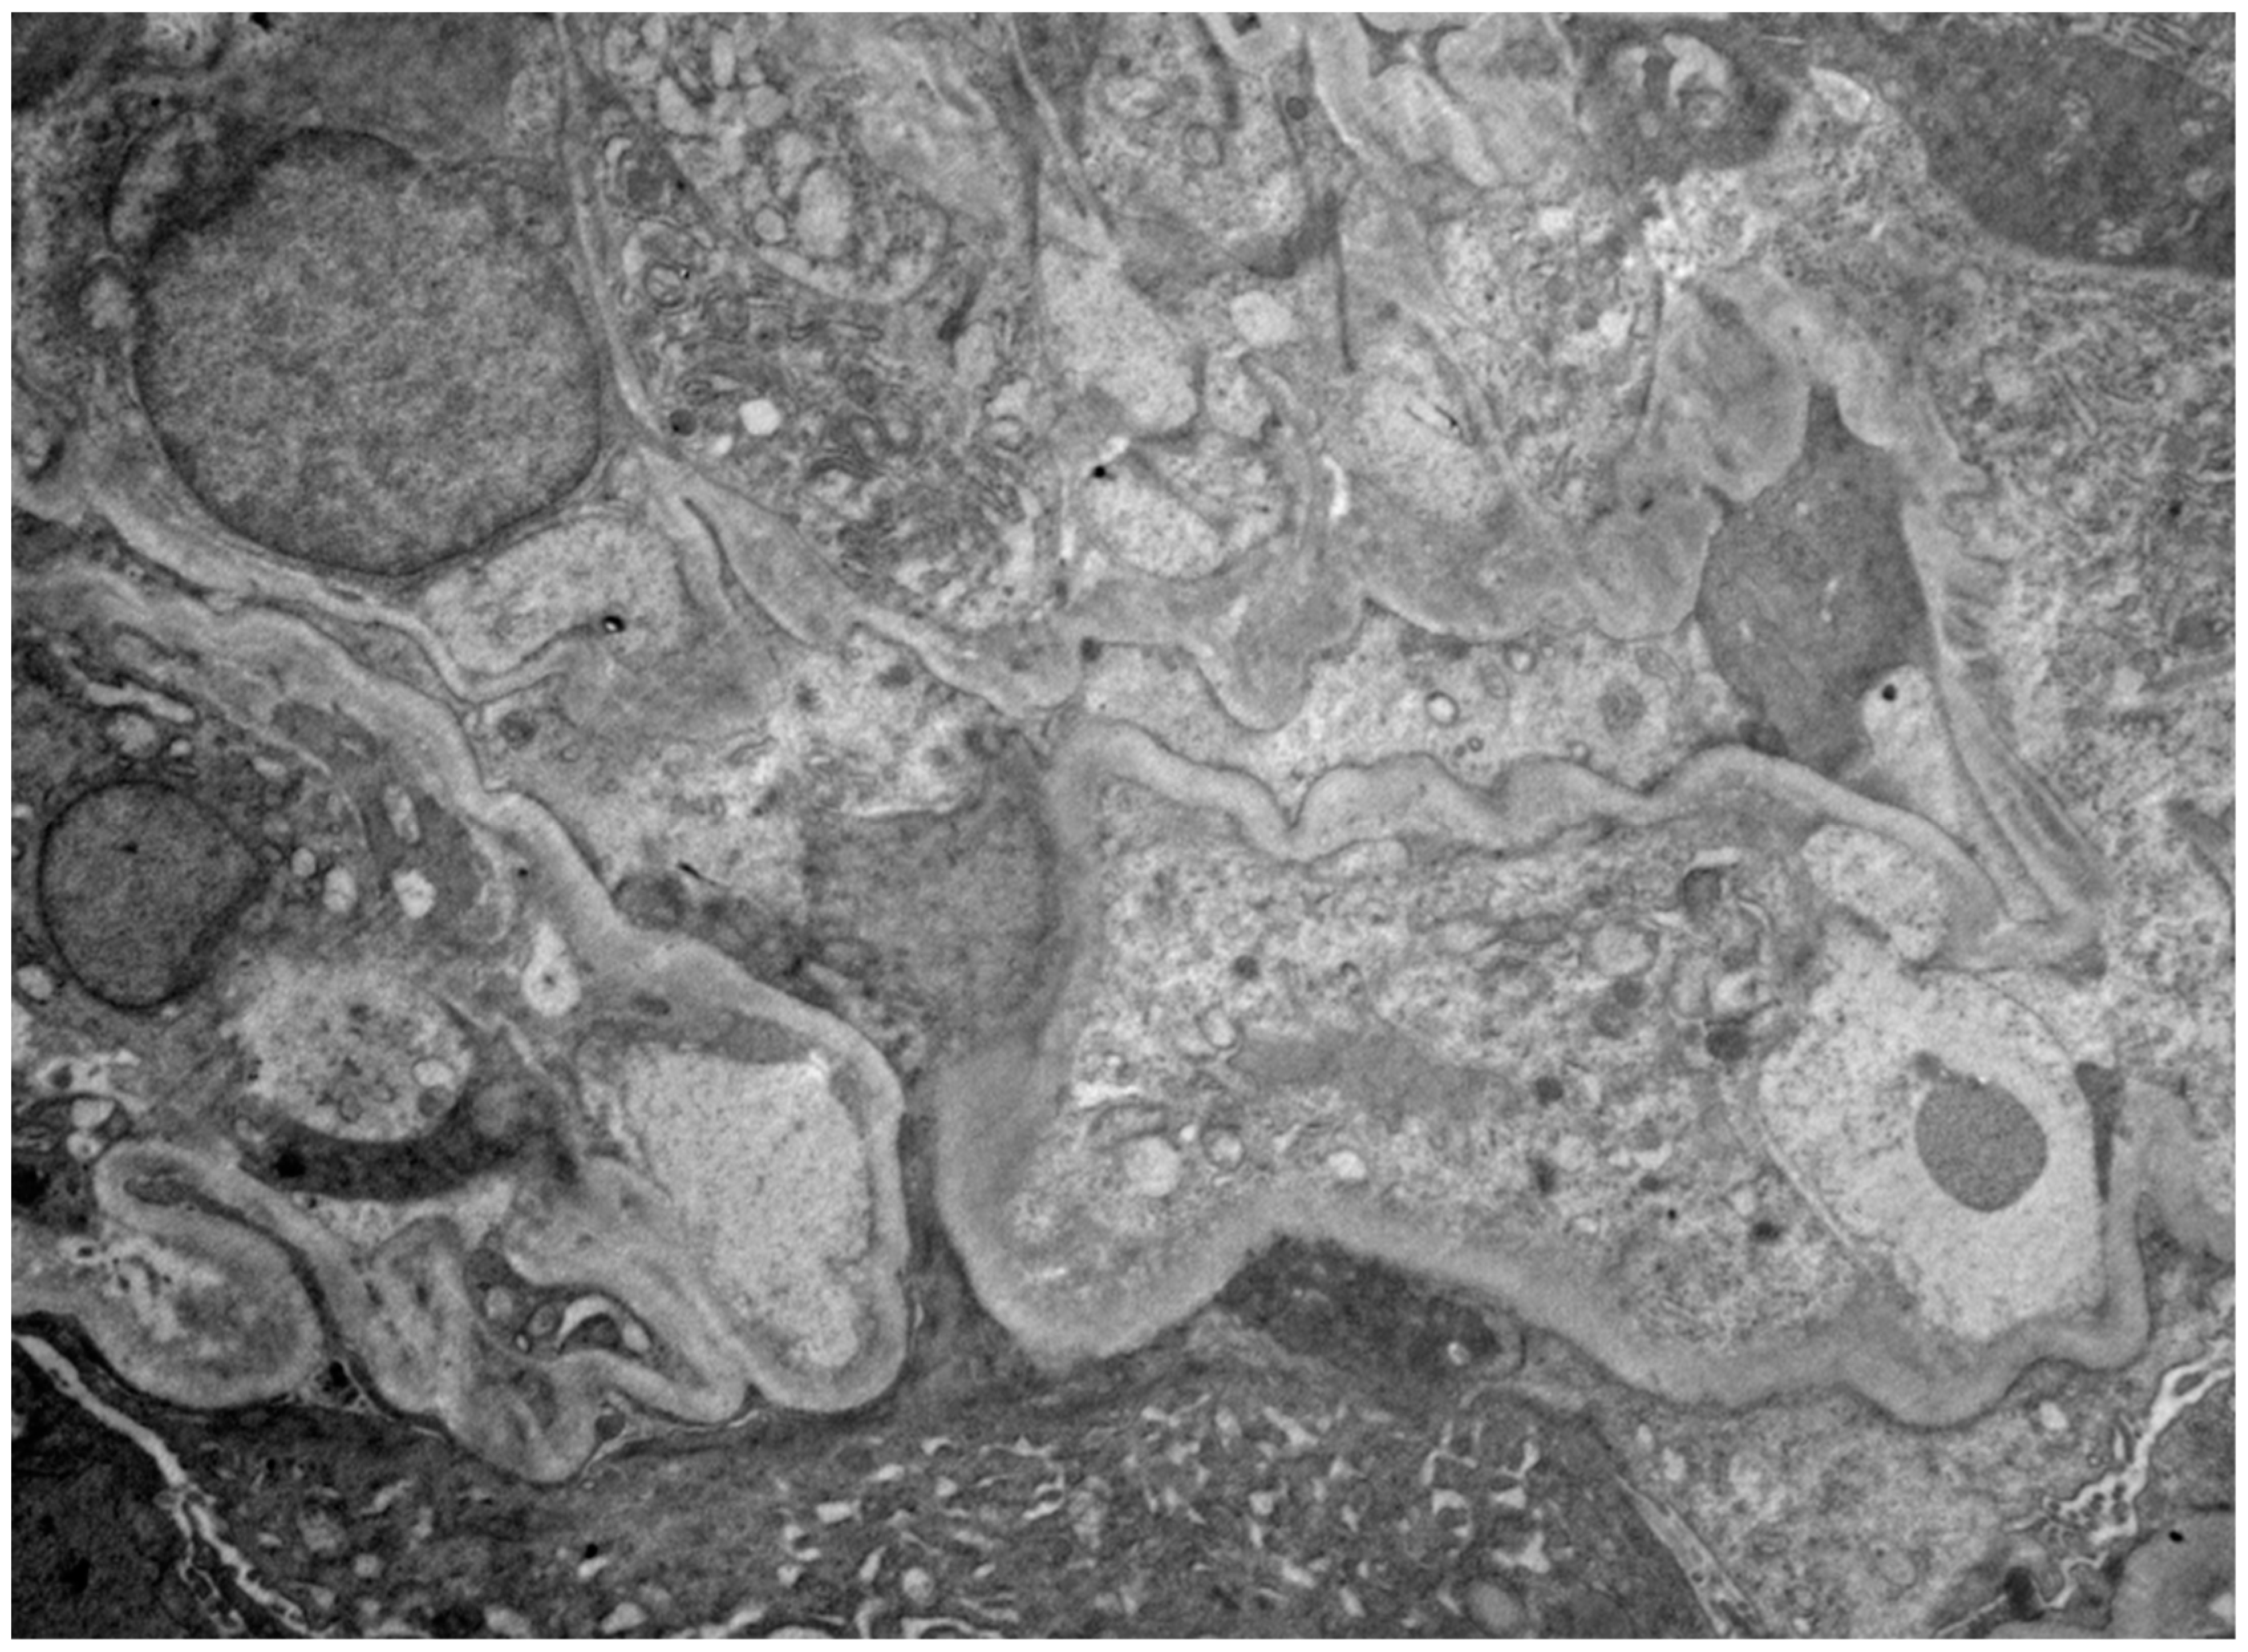

2. Case Presentation